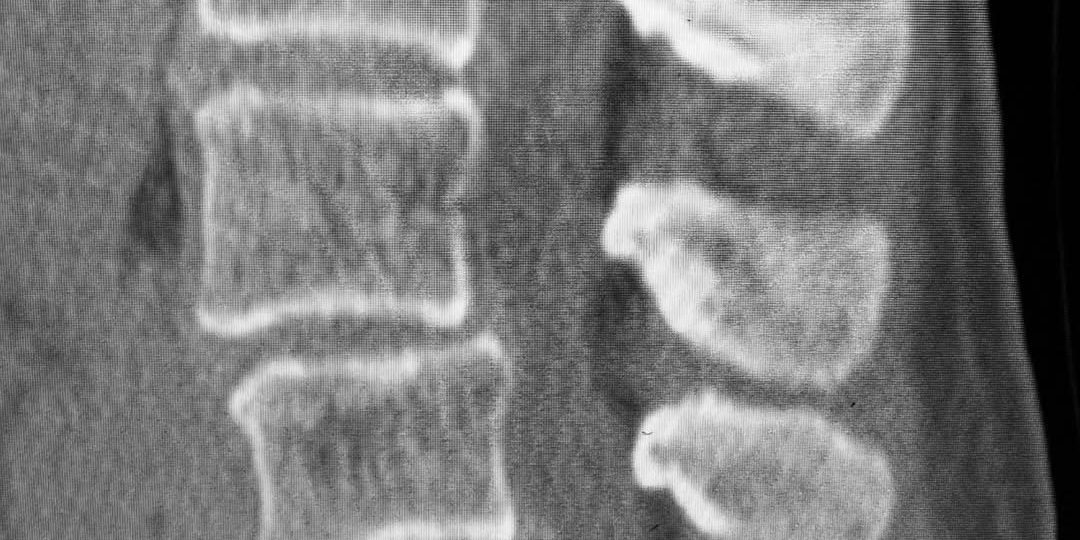

Lin underwent a complex two-level lumbar fusion at Texas Neuro-Spine Surgery. The procedure involved an anterior lumbar interbody fusion (ALIF) at L3-4 and L4-5, followed by laminectomies and pedicle screw instrumentation at the same levels. These surgeries were performed to help address her back issues and improve her mobility.